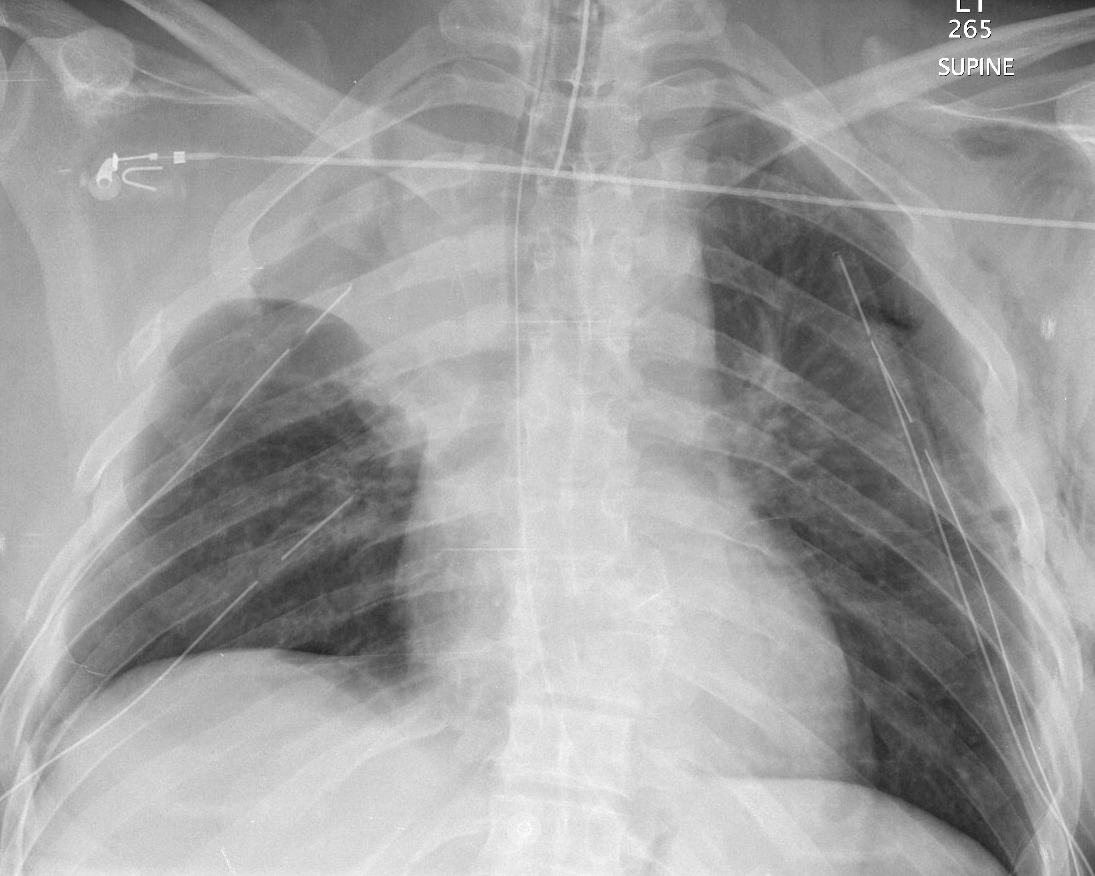

Gallery Blunt Chest Trauma Spine trauma Case 5a

Case 5a